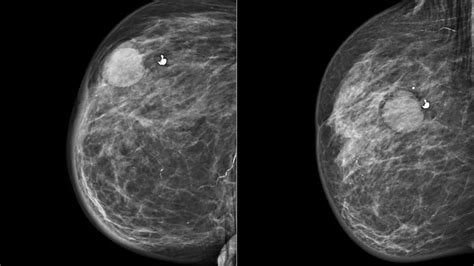

• Quistes mamarios: Son sacos llenos de líquido dentro de la mama. Son muy comunes y generalmente benignos.

Aunque un médico experimentado puede identificar muchos quistes mediante una simple inspección física y palpación, en ocasiones se requieren pruebas adicionales para confirmar el diagnóstico y asegurar que no se trata de otra patología. Las herramientas de diagnóstico incluyen ecografías, resonancias magnéticas o tomografías computarizadas. En casos donde existe duda sobre el contenido, el médico puede realizar una biopsia o aspiración con aguja fina.